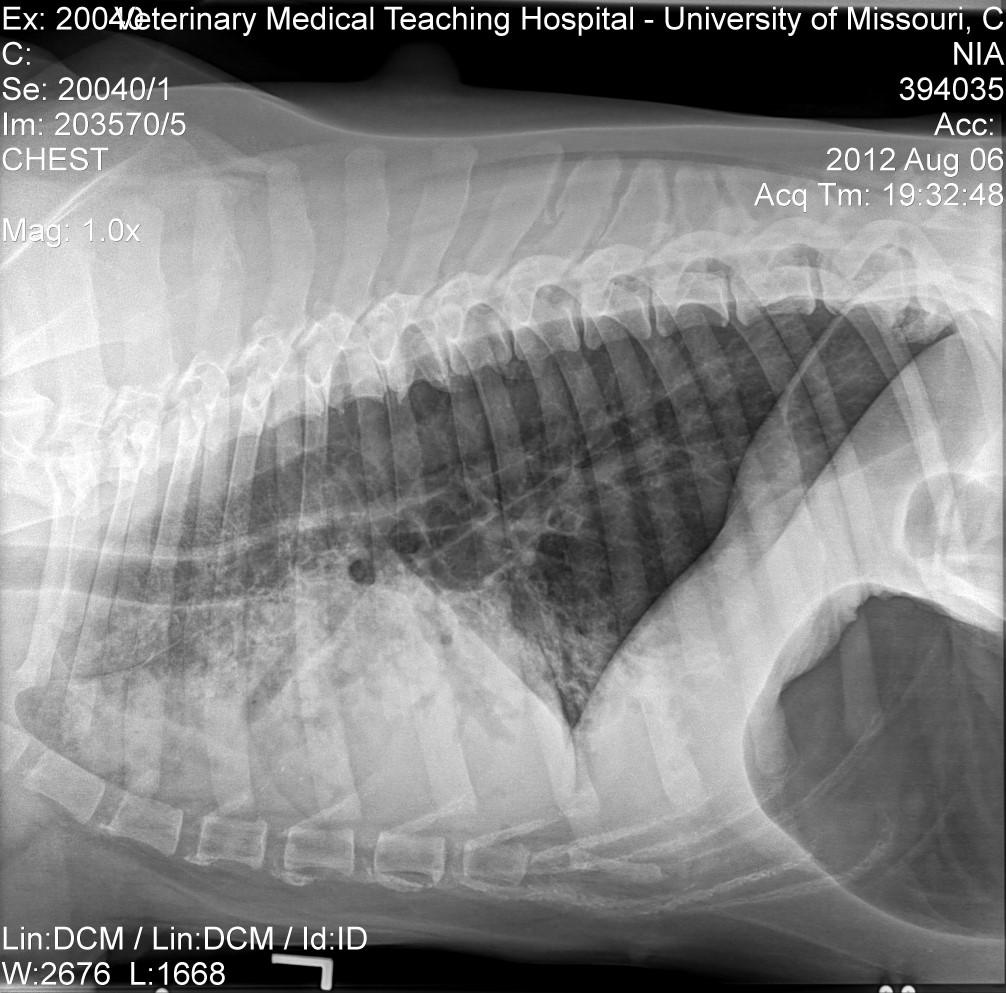

History:mostcommoninColliesandShetlandSheepdogs,lesionsmaystartearlyinlife,maywaxandwane;may havedysphagia(“dirtywaterbowls”),mayhave“high-stepping”gait,mayhavemuscleatrophyofheadandlimbs, mayhavemegaesophagusanddevelopaspirationpneumonia

Lesions:hairloss,scalingandcrustingonbridgeofnose,ears,tipoftail

Diagnosis:ruleoutotherdiseases,biopsiesofaffectedskinandmuscles(skin–vacuolarchangeinbasalcells, follicularatrophy,vasculopathy)